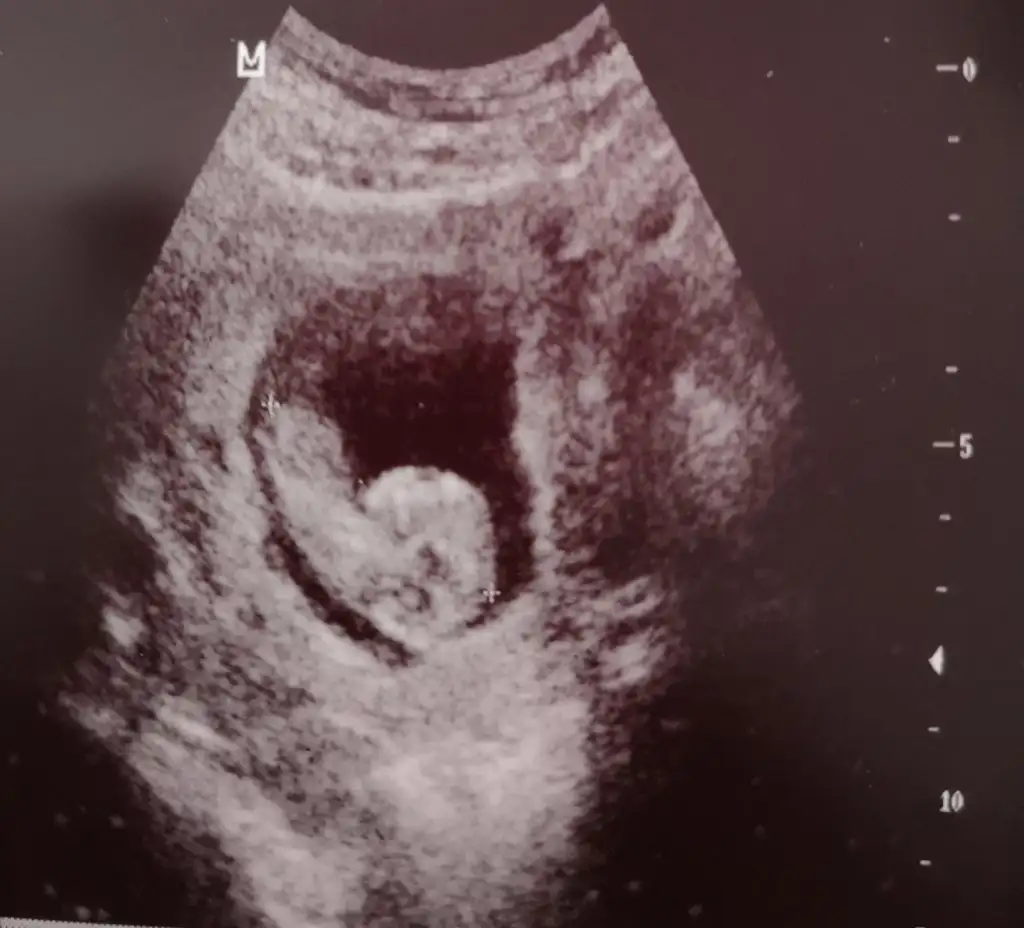

16+2 burda görüntü

@sip_sevdi bakın USG istemisimNuhu karşıya bakıyor kız gibi geldi bana başka USG varsa paylaşın 11 12 13 haftalar olmalı

Kaç haftalık USG 11 12 13 haftalar olmalı sanki erkek gibi başka USG varsa paylaşınMerhaba bunada bakabılırmısınız

Bu usg 11+4 haftalık , haftaya gidecegım cıbsıyet ogrenmeye 16 haftalık oluncaKaç haftalık USG 11 12 13 haftalar olmalı sanki erkek gibi başka USG varsa paylaşın